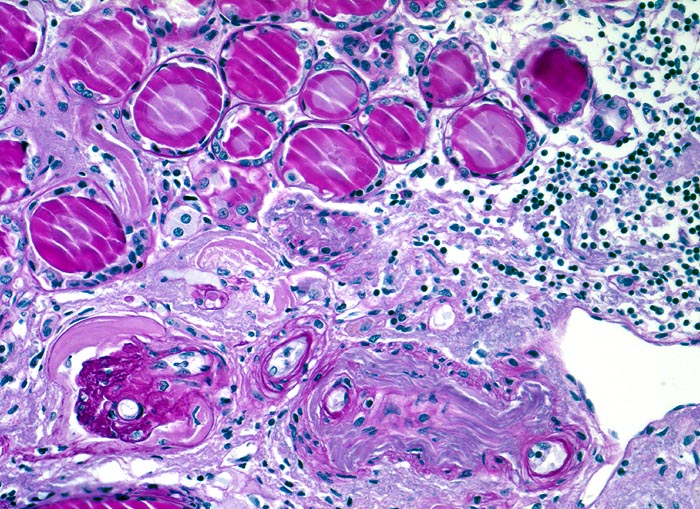

chronische Pyelonephritis: pyelonephritische Narbe

Oben im Bild Anschnitt eines Pseudostrumaherdes bestehend aus leicht dilatierten Tubuli mit abgeflachtem Epithel. Die Tubuli sind gefüllt mit eingedicktem kolloidartigem Sekret. Chronisches überwiegend lymphozytäres Entzündungsinfiltrat. Kleine Arterie mit massiver adaptativer Intimafibrose und daraus resultierender Stenosierung der Gefässlumina. Glomerulus mit kollabierten Kapillarschlingen und verdickter Bowman'scher Kapsel.

Makroskopisch ist die Nierenoberfläche grobhöckrig deformiert durch zahlreiche Narben mit teils rotem, teils weissem Grund. Beide Nieren sind verkleinert (Gewicht beider Nieren zusammen 180g). Das leicht ausgeweitete und gerötete Nierenbecken enthält mehrere kleine harte zackig begrenzte grauschwarze Kalziumoxalatsteine.

Nephrolithiasis und wiederholte akute pyelonephritische Schübe beidseits. Arterielle Hypertonie.